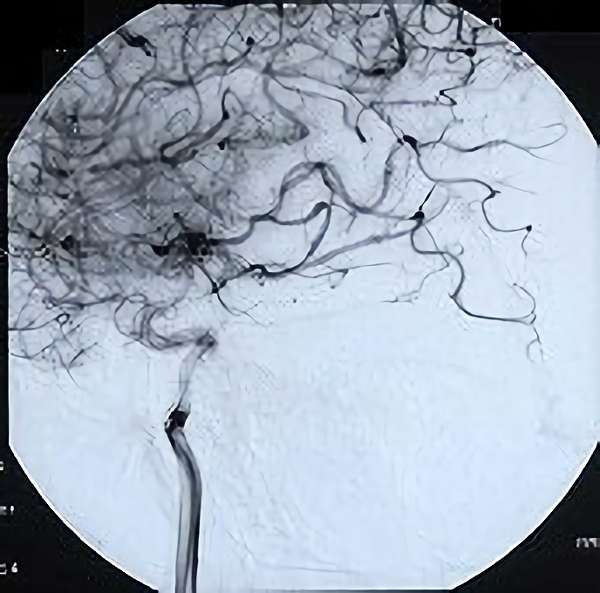

脳血管撮影

手術前